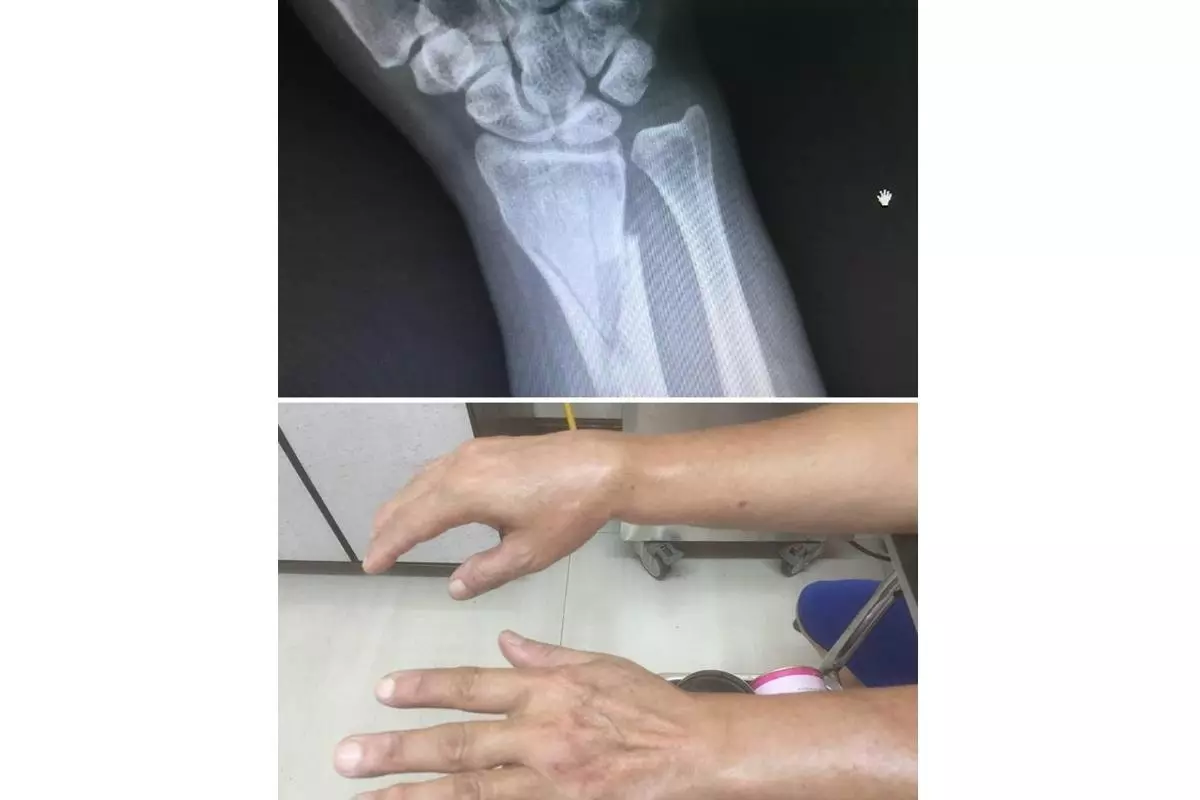

劍鳴損傷接骨院主要服務項目涵蓋骨折、骨頭移位、運動傷害、一般扭傷、身體酸痛、脫臼、五十肩、病理按摩、拉傷等各類筋骨問題。不論是上班族常見的肩頸僵硬、久坐引發的腰背痠痛,或是長輩行走不穩造成的跌倒受傷,以及運動族群常見的肌肉拉傷與關節不適,都能在此獲得專業協助。

※※※ 顧客案例分享 ※※※